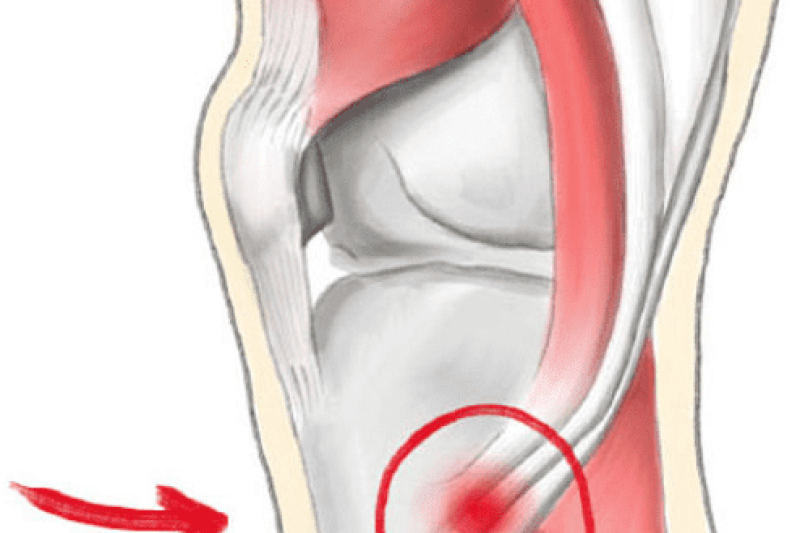

What is Pseudogout “false gout”? Calcium Pyrophosphate Deposition (CPPD) also known as Pseudogout, is a joint problem caused by crystals of calcium salt called Pyrophosphate that are deposited …